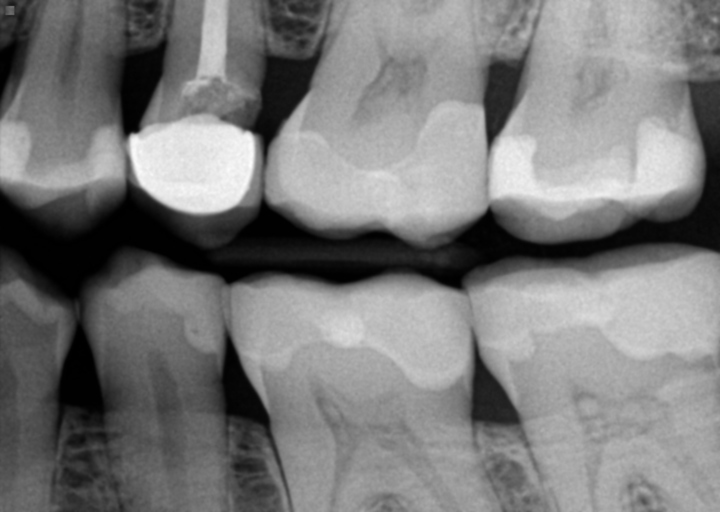

If your daughters dentist told you she needs crowns on her bicuspid teeth, I would seek a second opinion.  The primary dentition does not have bicuspids.  They are some of the last teeth to erupt and children will not begin to see them until they are close to 11 years old.  The bicuspids replace the primary molars in the permanent dentition.  If your daughter has primary teeth with caries, it is best to have them restored as quickly as possible and implement a good oral hygiene program.  Early prevention is key to keeping your teeth healthy.

Cavity under crown or ill fitted crown?

I have received conflicting opinions on a tooth: one dentist said it is cavity under the crown and treatment could be crown lengthening/dental implant while other dentist said there is no cavity, it's just ill fitted crown. Is this something we can...